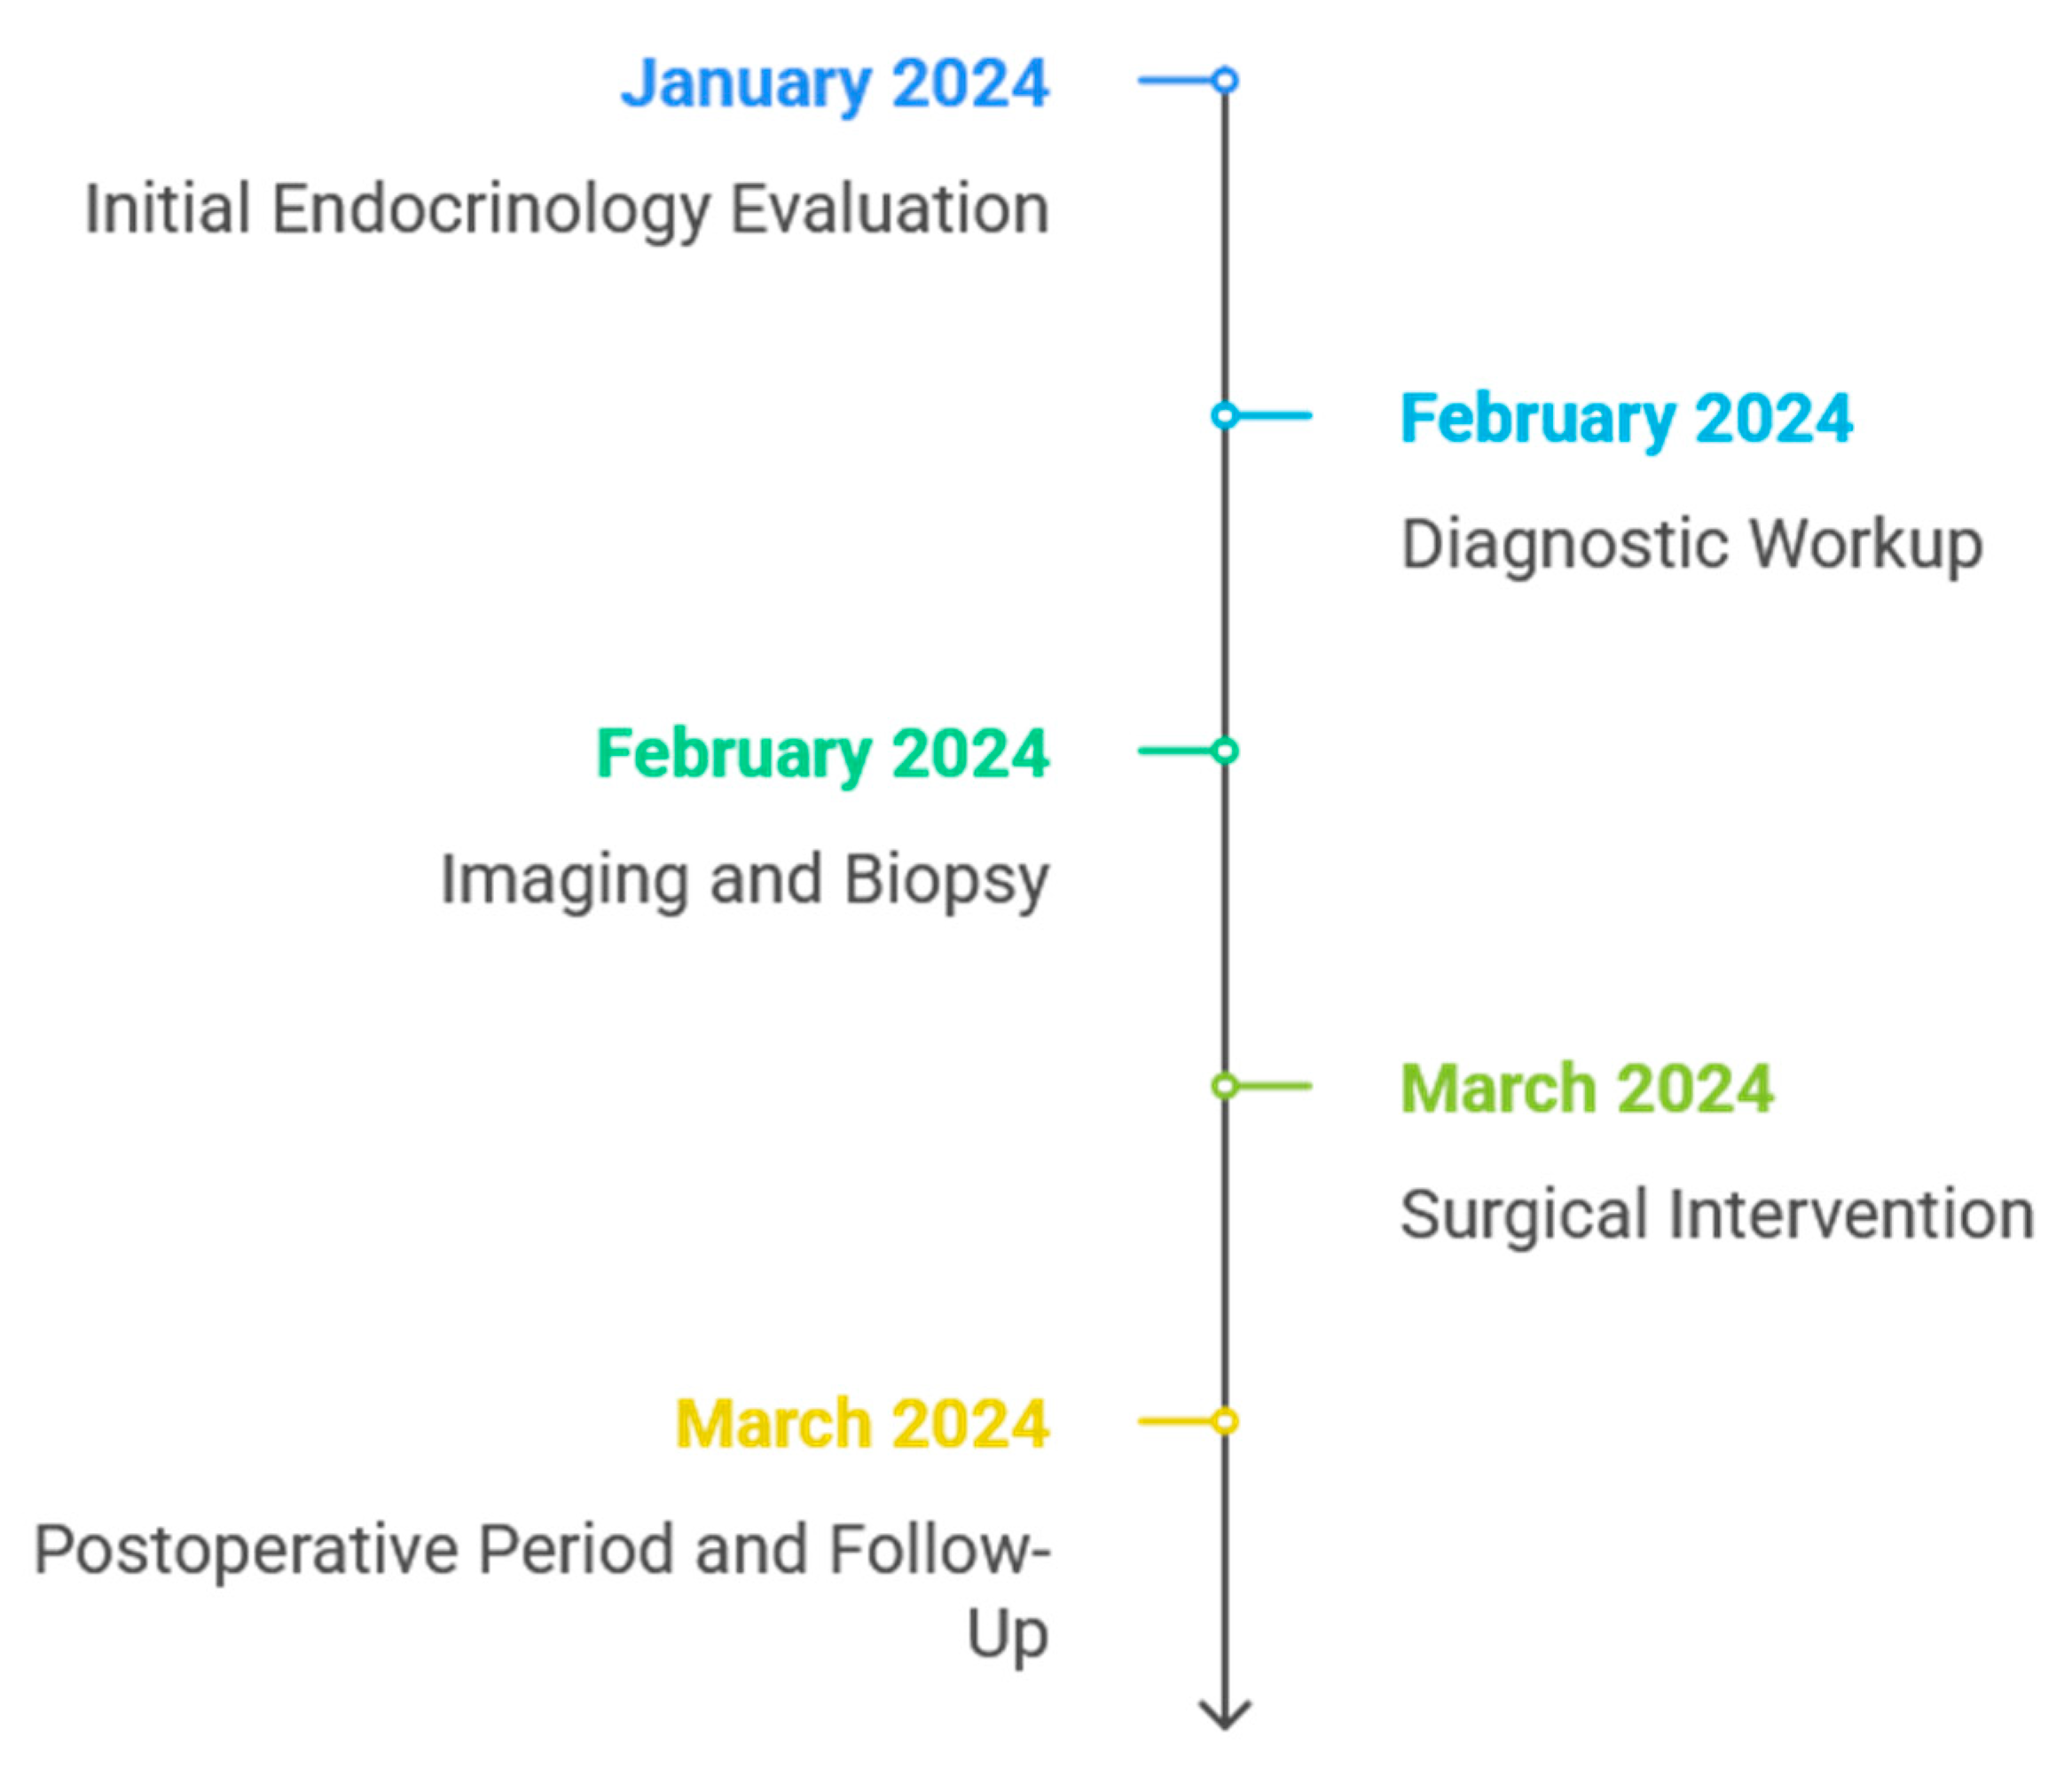

1. Introduction and Clinical Significance

2. Case Presentation

2.1. Initial Diagnosis and Early Management

2.2. Endocrinology Evaluation

2.3. Diagnostic Procedures

2.4. Surgical Intervention and Intraoperative Findings

2.5. Postoperative Follow-Up and Clinical Evolution